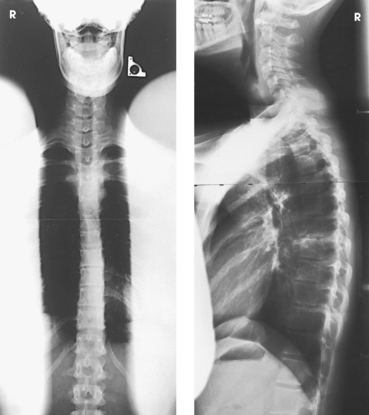

Fig. 2-1 A-C, Body structures with significantly varied tissue thickness and density include thoracic spine (AP) (A), hip (lateral) (B), and cervicothoracic region (lateral) (C). Note different thicknesses in these areas. Use of compensating filters allows these structures to be shown with one exposure.

• The scoliosis filters are used with two of the most challenging projections to obtain: the PA (Frank et al. method) and lateral full-spine projections for evaluation of spinal curvatures. These projections are challenging because the cervical, thoracic, and lumbosacral spines have to be shown on one image. One exposure technique has to be set for what normally would be three separate exposures. With the use of compensating filters, the PA projection can be made with a wedge filter positioned over the cervical and thoracic spines (Fig. 2-13, A). For the lateral projection, two double-wedge filters are positioned over the mid-thoracic area and the cervical spine (Fig. 2-13, B). The exposure technique for the PA and lateral projections is set to penetrate the most dense area—the lumbar spine. The filters attenuate enough of the exposure over the cervical and thoracic areas to show the thoracic and cervical spines adequately.